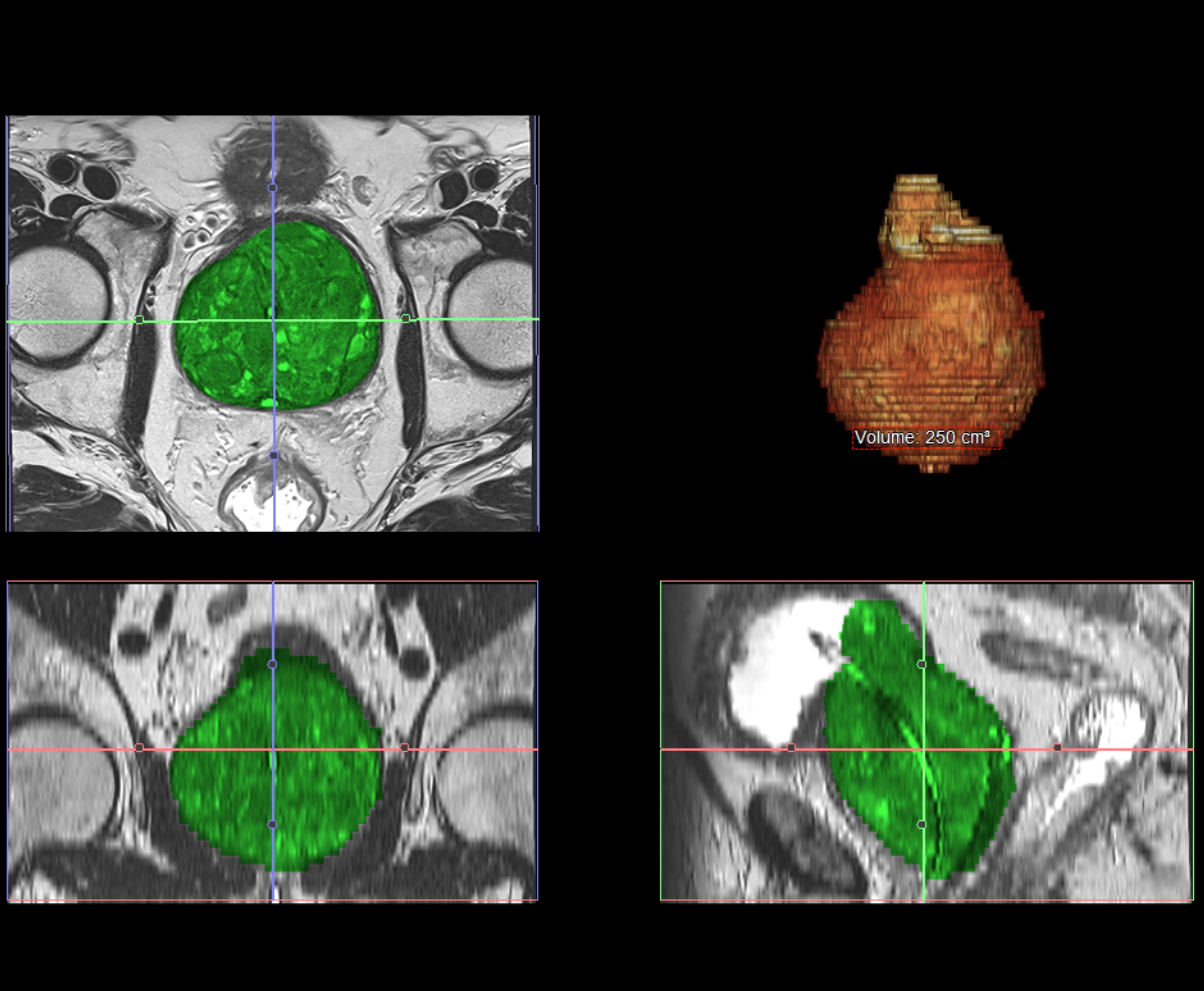

The normal prostate in young adult men typically weighs 20-30 grams (about the size of a walnut). With BPH, the prostate can enlarge significantly, ranging from 30-40 grams in mild cases to over 100 grams in severe cases. Some men develop massive prostatic enlargement exceeding 200 grams, known as "giant prostatomegaly," which can pose significant treatment challenges with traditional techniques.